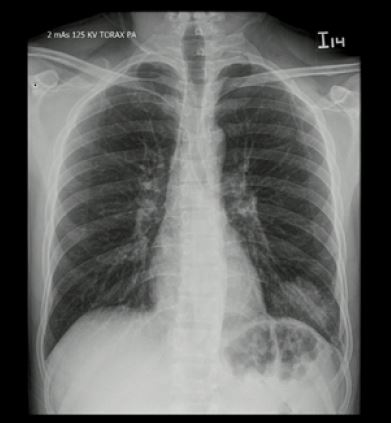

El caso corresponde a un hombre de 34 años de edad, natural de Valledupar y procedente de Bogotá, con diagnóstico de infección por VIH estadio 3 con adecuado control inmunovirológico, quien acudió al servicio de urgencias con un cuadro clínico de 4 días de evolución, caracterizado únicamente por singulto. No se encontraron datos positivos a la revisión por sistemas y no tenía otros antecedentes médicos relevantes. En el examen físico no se encontraron hallazgos significativos. Inicialmente, se manejó con haloperidol por vía intravenosa a una dosis de 2,5 mg cada 8 h durante 2 días, y posteriormente recibió metoclopramida a dosis de 10 mg por vía intravenosa cada 12 h durante 5 días sin presentar mejoría. Durante su estancia se registró un pico febril de 39 ºC. Dentro de los exámenes de extensión se evidenció leucocitosis y neutrofilia. La radiografía de tórax mostró una radiopacidad de ocupación alveolar en la base pulmonar izquierda en la proyección anteroposterior ( figura 1), también vista en la proyección lateral ( figura 2). Se consideró que el paciente se encontraba cursando una neumonía adquirida en comunidad, por lo cual se inició terapia antibiótica con ampicilina sulbactam y claritromicina. Sin embargo, ante un cuadro clínico poco claro, se decidió caracterizar el hallazgo radiológico mediante una tomografía de tórax de alta resolución, que confirmó que la ocupación alveolar se trataba de una consolidación ( figura 3). Tras 48 h de iniciada la terapia antibiótica, el singulto se resolvió. El informe final de los hemocultivos fue negativo y la evolución del paciente fue adecuada, por lo que se indicó egreso con control imagenológico en 6 semanas.